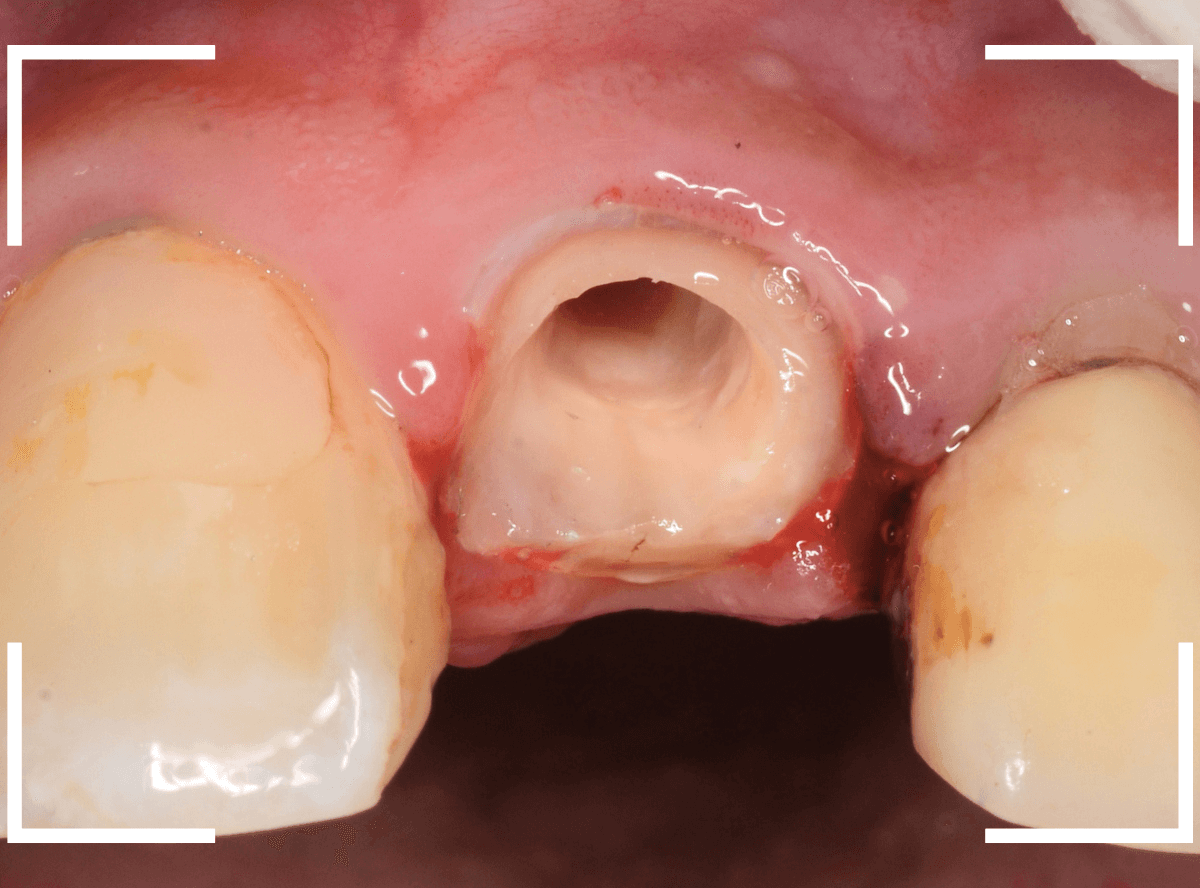

そして、後ろの歯との境の〇部には汚れや歯石が多くつまっています。

虫歯と共に、歯の周りの縁下歯石除去も行いました。

歯の周りがきれいになっているのがわかると思います。